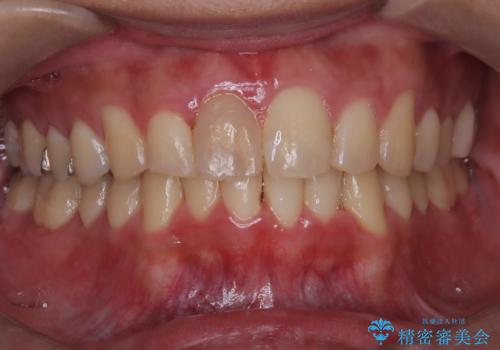

【インビザライン 非抜歯】歯の捻じれと歯のでこぼこを治したい!

- 「上の前歯の捻じれと下の前歯のでこぼこを治したい」を主訴に来院された患者様です。

矯正検査の結果、非抜歯で矯正可能だったためインビザラインで治療を行いました。

アーチの拡大とIPRで叢生を改善いました。

11ヵ月で矯正を終える事ができ患者様も大変ご満足されていました。